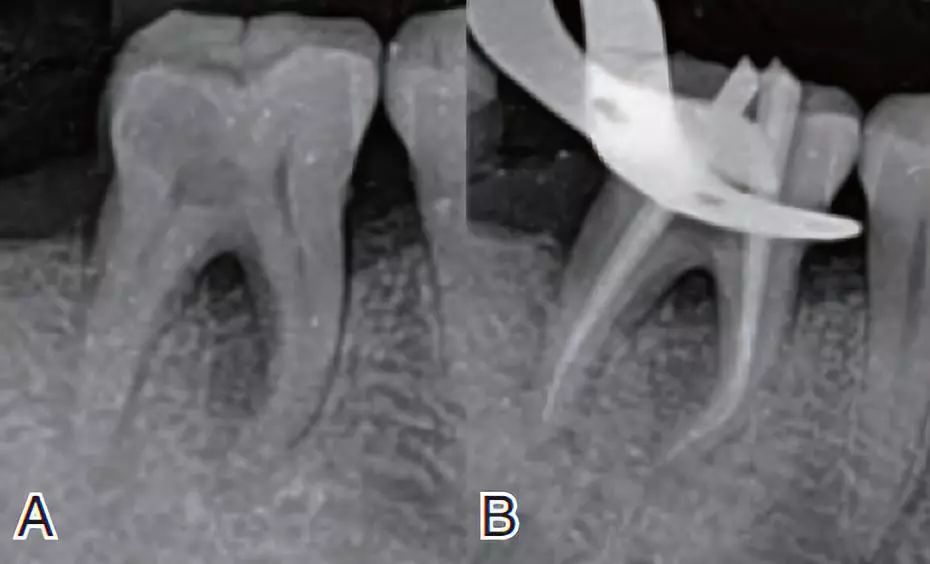

关于双下6根管拍摄及认知